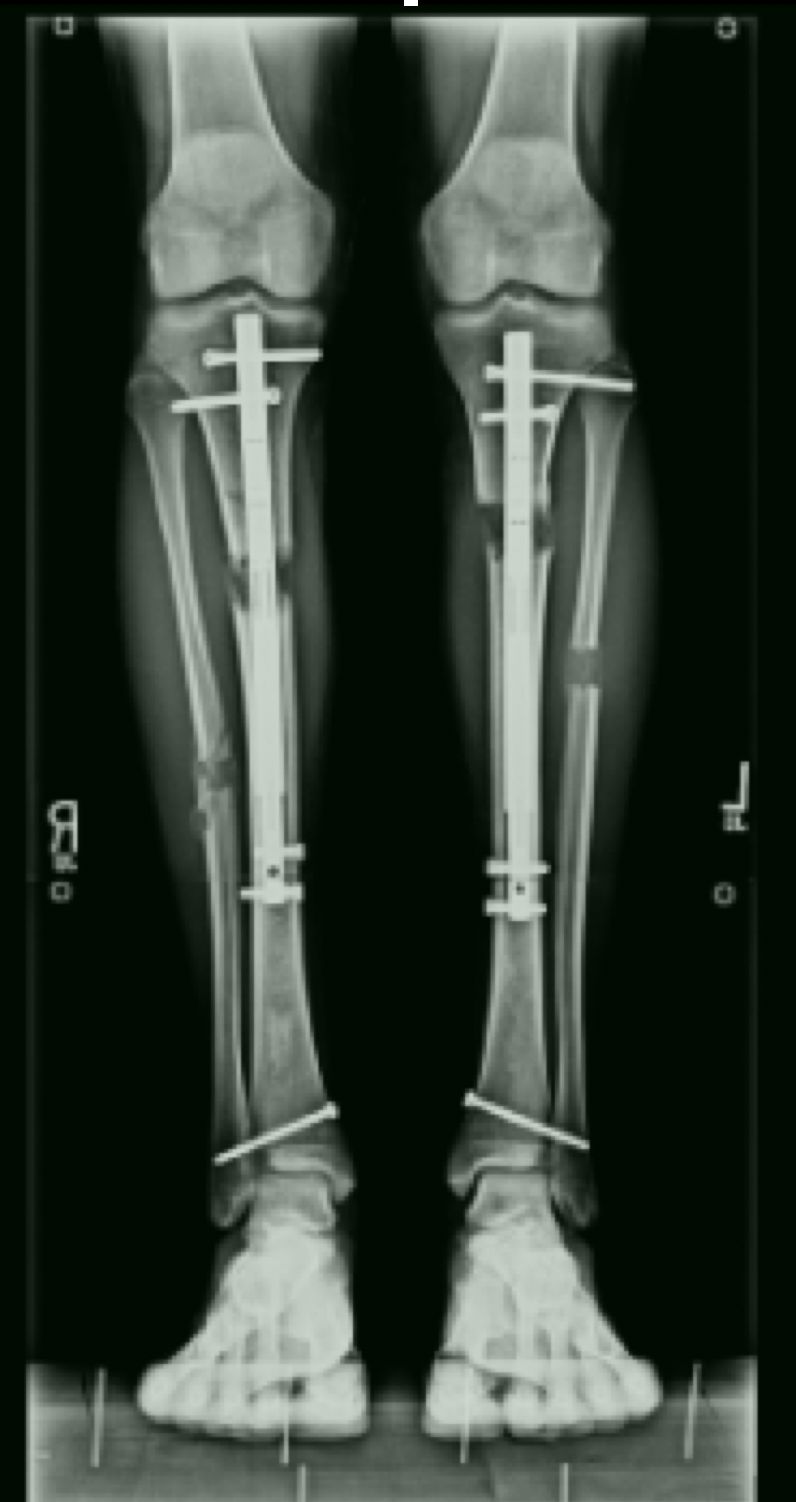

Jestem chirurgiem specjalizującym się w zaawansowanych rekonstrukcjach stawów oraz wydłużaniu kończyn dolnych (limb lengthening and reconstruction surgery). Kompleksowo opiekuję się osobami z problemami o podłożu ortopedycznym oraz neurologicznym, szczególnie dzieci z wadami wrodzonymi i schorzeniami nerwowo-mięśniowymi. Dzięki wieloletniemu doświadczeniu w nowoczesnych technikach rekonstrukcyjnych znacząco udoskonaliłem metody chirurgicznego leczenia dzieci z problemami neurologicznymi, otwierając przed nimi nowe możliwości poprawy funkcjonalności oraz jakości życia. Specjalizujemy się w jednoczasowych wielopoziomowych rekonstrukcjach kończyn (SEMLS) oraz kompleksowych rekonstrukcjach stawów biodrowych, łącząc sprawdzone techniki operacyjne z innowacyjnymi rozwiązaniami. Oprócz leczenia operacyjnego, koordynuje leczenie zachowawcze, obejmujące wielopoziomowe podania toksyny botulinowej (BTX) oraz minimalnie inwazyjne procedury, takie jak SPML (Selective Percutaneous Myofascial Lengthening) czy PERCS (Percutaneous Muscle Lengthening). Każdy pacjent otrzymuje indywidualnie opracowany program terapeutyczny, którego celem jest osiągnięcie najlepszych efektów przy minimalnym obciążeniu. Opiekuję się również pacjentami dorosłymi wymagającymi endopiotezoplastyki stawów oraz ratowaniem kończyn przed amputacją z powodu aktywnej lub przewlekłej infekcji W mojej pracy kluczowe jest podejście holistyczne, które łączy zaawansowane techniki chirurgiczne z terapią zachowawczą, aby zapewnić pacjentom kompleksową opiekę oraz trwałe efekty leczenia. Powierzenie nam zdrowia pacjentów jest dla nas ogromną odpowiedzialnością, a jednocześnie najwyższym zaszczytem. Zakres mojej specjalizacji obejmuje leczenie: 1. Wady wrodzone i rozwojowe kończyn: Hemimelia strzałkowa, niedorozwój kości udowej (CFD – Congenital Femoral Deficiency) – zaawansowane metody rekonstrukcyjne, w tym wydłużanie oraz procedury typu SUPERhip, SUPERankle Brak kości promieniowej i inne deformacje kończyny górnej – zabiegi ulnaryzacji, pollicyzacji, korekcji osi Mnogie wyrośla chrzęstno-kostne (MHE) – chirurgiczna korekcja deformacji i zapobieganie wtórnym ograniczeniom ruchomości Wrodzony staw rzekomy kości piszczelowej (CPT) – rekonstrukcja podudzia metodą CPT Xunion 2. Zaburzenia osi i długości kończyn: Skrócenia kończyn – techniki wydłużania z zastosowaniem gwoździ teleskopowych, aparatów Ilizarowa oraz STRYDE i PRECICE Zaburzenia osi kończyn (koślawość, szpotawość, rotacje) – korekcje wielopłaszczyznowe, osteotomie oraz stabilizacja z użyciem aparatów zewnętrznych i gwoździ wewnętrznych 3. Neuroortopedia – leczenie pacjentów z zaburzeniami neurologicznymi: Mózgowe porażenie dziecięce (MPD) – operacje zmniejszające spastyczność, korekcje stawów oraz zabiegi wielopoziomowe poprawiające funkcję chodu Przepuklina oponowo-rdzeniowa (spina bifida) – leczenie deformacji stóp i kończyn dolnych, stabilizacja stawów Artrogrypoza – wieloetapowe leczenie chirurgiczne poprawiające zakres ruchu i funkcjonalność kończyn 4. Zakażenia i zaburzenia zrostu kostnego: Osteomyelitis (zakażenia kości i szpiku) – leczenie chirurgiczne i antybiotykoterapia celowana Zaburzenia zrostu kostnego, brak zrostu (non-union, mal-union) – nowoczesne techniki transportu kostnego, przeszczepów i stabilizacji 5. Rekonstrukcja dużych stawów i leczenie deformacji: Endoprotezoplastyka biodra, kolana i stawu skokowego – zarówno w przypadkach zwyrodnieniowych, jak i pourazowych Choroba Legg-Calvé-Perthesa – metody operacyjne poprawiające ukrwienie głowy kości udowej i ograniczające deformację Złuszczenie głowy kości udowej (SCFE – Slipped Capital Femoral Epiphysis) – leczenie za pomocą zmodyfikowanej metody Dunna, pozwalającej na anatomiczną rekonstrukcję biodra i zachowanie funkcji stawu Dysplazje szkieletowe – interdyscyplinarne podejście do leczenia deformacji i ograniczeń funkcjonalnych 6. Leczenie stopy cukrzycowej i deformacji stóp: Stopa cukrzycowa – nowoczesne techniki rekonstrukcji stopy, zapobieganie amputacji Deformacje stopy (np. stopa końsko-szpotawa, płasko-koślawa, stopa sierpowata) – korekcja chirurgiczna i indywidualne podejście do biomechaniki chodu 7. Chirurgia urazowa dzieci i dorosłych: Leczenie złamań z zastosowaniem minimalnie inwazyjnych technik operacyjnych Rekonstrukcja kończyn po urazach, w tym ratowanie kończyny zagrożonej amputacją Stabilizacja wewnętrzna i zewnętrzna złamań patologicznych oraz pourazowych 8. Osseointegracja - zaopatrzenie pacjentów po amputacji poprzez korekcję kikuta lub aplikację osseointegracji do kości powyżej lub poniżej kolana wraz z zaopatrzeniem prtotetycznym 9. Wydłużanie kosmetyczne kończyn dolnych i górnych. Wykonujemy jednoczasowe operacje zarówno wydłużania kości udowych i piszczelowych jako jedyny ośrodek w Europie. Efekt jaki możemy uzyskać to 10-12 cm zwiększenia wzrostu. Wierzę, że najlepsze efekty leczenia można osiągnąć dzięki współpracy grona specjalistów, kierując się zasadą pacjentocentryzmu, która stawia potrzeby pacjenta w centrum procesu terapeutycznego.. Dlatego każda konsultacja odbywa się w interdyscyplinarnym zespole, w skład którego wchodzą ortopedzi, fizjoterapeuci, ortotycy i terapeuci zajęciowi. Pierwsza wizyta trwa około 1,5 godziny i obejmuje szczegółową ocenę stanu zdrowia oraz opracowanie planu leczenia chirurgicznego. W naszym instytucie działamy na podstawie indywidualnie opracowanych dla każdej jednostki chorobowej protokołów leczenia operacyjnego oraz postępowania fizjoterapeutycznego, których jestem współautorem. Dzięki temu zapewniamy spójne, kompleksowe i skuteczne podejście terapeutyczne, dostosowane do specyfiki danej choroby i indywidualnych potrzeb pacjenta. Zapraszam na konsultacje ortopedyczne, neuroortopedyczne oraz deformacyjne.